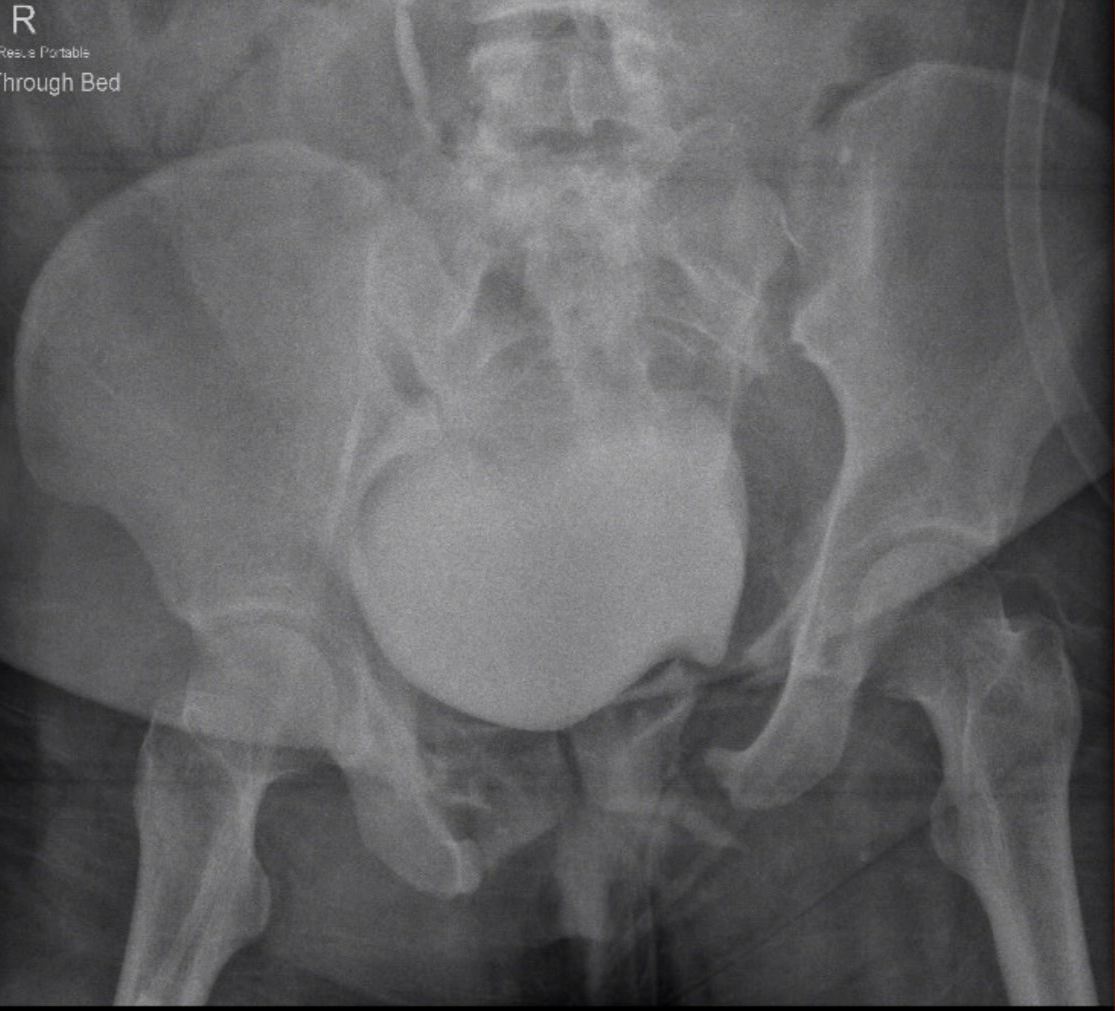

• Unstable pelvic ring fractures

• Acetabular fractures with displacement